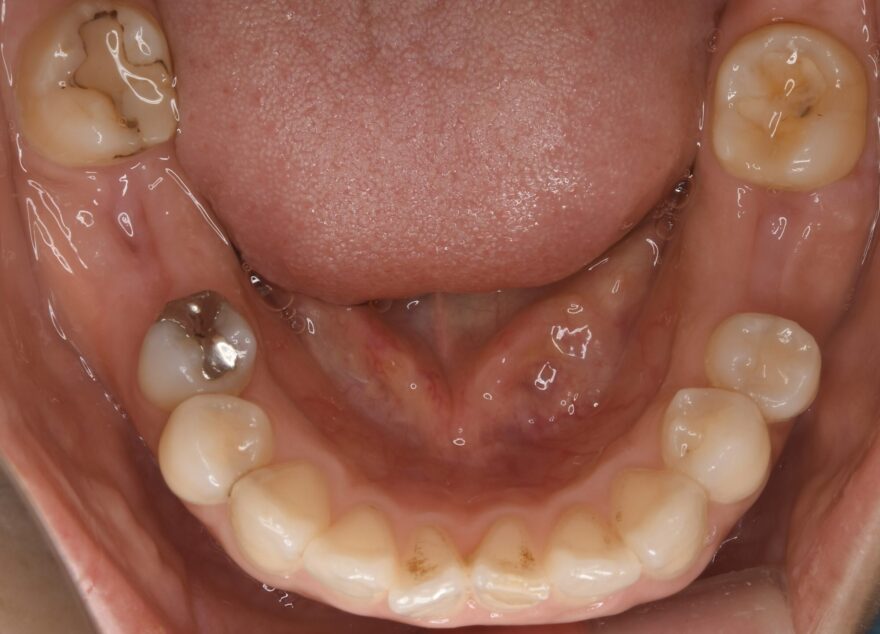

初診時のレントゲン写真